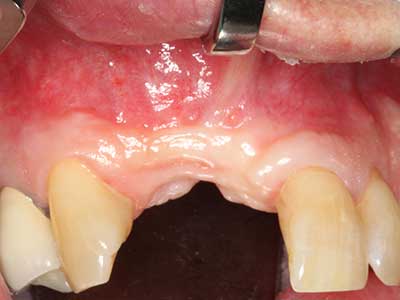

La piezochirurgia presenta altri vantaggi per quanto riguarda la raccolta di blocchi ossei. Oltre all'elevata precisione dell'osteotomia appena descritta, l'utilizzo di puntine per sega molto sottili permette di minimizzare in maniera significativa la perdita di materiale. È molto probabile che si verifichi una maggiore perdita di materiale durante la raccolta utilizzando puntine di strumenti più spessi, in particolare delle frese Lindemann (Lakshmiganthan, Gokulanathan et al. 2012). La separazione basale, necessaria in particolare per i trapianti di blocchi nella zona retromolare, viene semplificata grazie a seghe specificatamente progettate di forma rettangolare; di conseguenza la piezochirurgia è considerata una procedura precisa, semplice e sicura per la raccolta di blocchi di osso nella zona retromolare (Happe 2007) (figg. 1-12).

Indicazione: incisione ossea

Il tessuto osseo non è semplicemente una struttura minerale, ma contiene anche una percentuale significativa di fibre di collagene. Ciò significa che non possiede solo una buona forza di compressione, ma anche un certo livello di flessibilità che è possibile sfruttare durante l'esecuzione degli accrescimenti di osso. Nella procedura di espansione classica con incisione ossea, la cresta alveolare atrofizzata viene incisa longitudinalmente ed espansa con cautela dopo aver raggiunto una profondità di osteotomia adeguata (figg. 13-16), idealmente senza una sostanziale rimozione del periostio (Brugnami, Caiazzo et al. 2014, Stricker, Fleiner et al. 2014). I sistemi a piastra e vite con distanza di espansione incrementale si sono dimostrati efficaci nella separazione delle due lamelle ossee restando al di sotto della soglia di frattura. In generale, sono richieste larghezze dell'osso residuo di almeno 3-4 mm (Chiapasco, Zaniboni et al. 2006) per garantire un'adeguata flessibilità e una copertura sufficiente dell'osso per gli impianti futuri. Se necessario, un'osteotomia di rilascio verticale su uno o più lati può migliorare la flessibilità. Una combinazione con ulteriori tecniche di accrescimento, in particolare dal lato buccale, è stata descritta come un'alternativa alla tecnica classica.

La procedura di incisione è particolarmente atraumatica e non comporta una perdita significativa di dimensione durante l'utilizzo delle seghe piezoelettriche, così come non si notano differenze rilevanti tra impianti in mandibole incise e impianti in una cresta alveolare senza deficit osseo (Chiapasco, Zaniboni et al. 2006, Danza, Guidi et al. 2009). Una sufficiente irrigazione continua è essenziale, tuttavia, in particolare con incisione profonda e localmente ristretta, per prevenire la sollecitazione termica nelle regioni apicali dell'osteotomia.